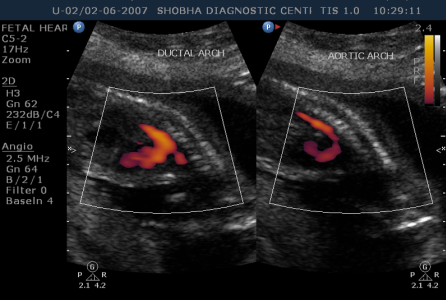

- Thorough scanning of your baby is done to know if baby is developing normally or not. Special attention is paid to brain, face, spine, heart, stomach, bowel, kidneys & limbs.